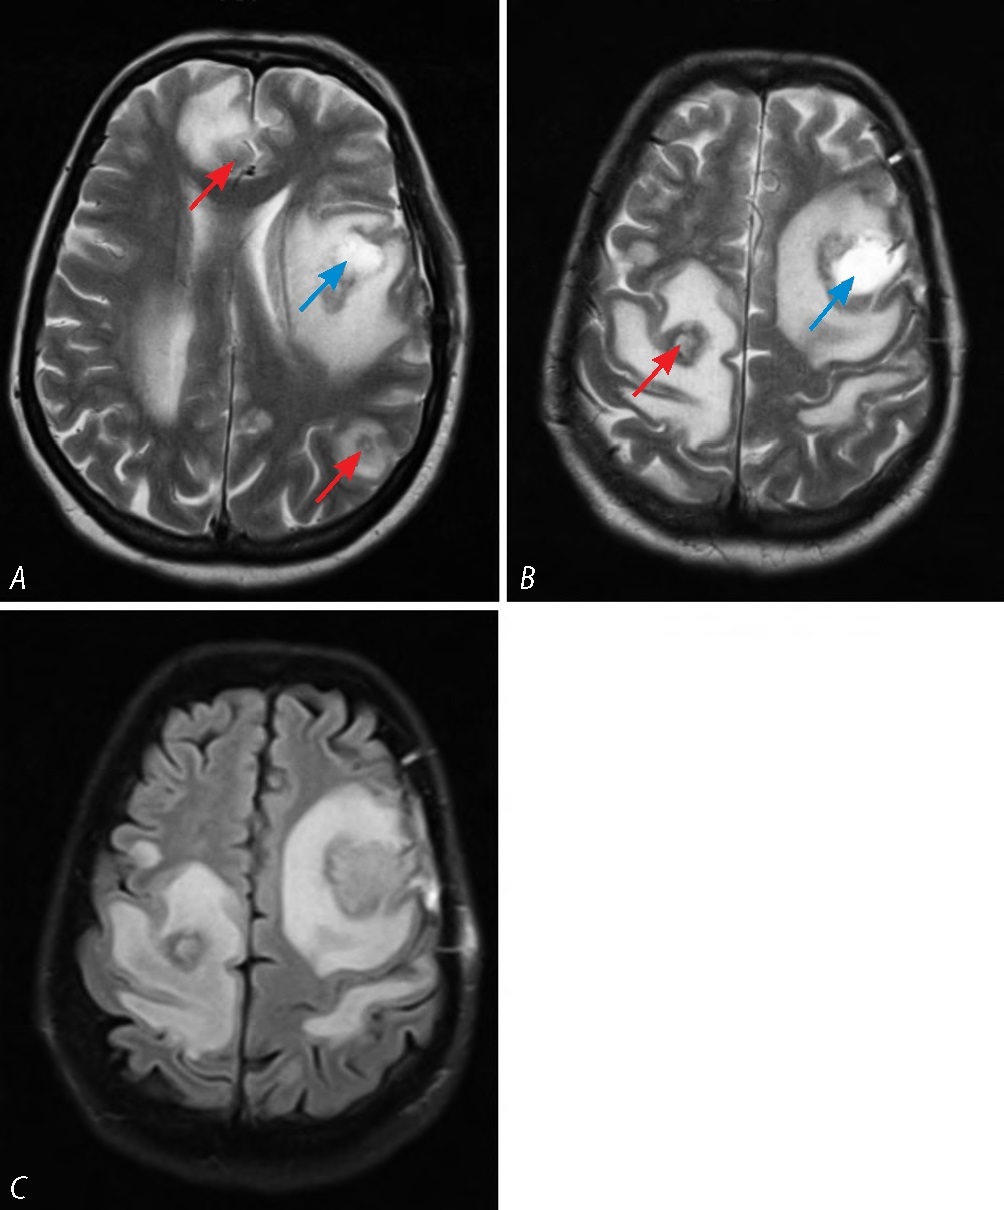

Через 1 сут, после стабилизации состояния, выполнена МРТ головного мозга. Выявлены гипоинтенсивные на Т2 и изоинтенсивные на Т2-FLAIR внутримозговые очаги с выраженным перифокальным отёком, гиперинтенсивная на Т2 и изоинтенсивная на T2-FLAIR послеоперационная киста левой лобной доли. Кроме того, визуализированы несколько внутримозговых гиперинтенсивных на Т2 и Т2-FLAIR очагов (рис. 4).

Рис. 4. МРТ головного мозга пациентки Р. в режимах Т2-ВИ (А, В) и FLAIR (С) через 1 мес после операции.

Определяются гипоинтенсивные очаги с выраженным перифокальным отёком (красные стрелки), гиперинтенсивная послеоперационная киста (синие стрелки).

Fig. 4. Т2 weighed (А, В) and FLAIR (С) brain MRI images of female patient R. one month postoperatively.

Hypointensive foci with significant perifocal edema (red arrows) and a hyperintensive postoperative cyst (blue arrows).